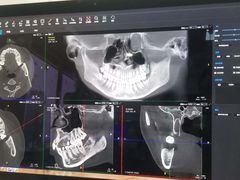

• Dr.Z dental仁康种植矫正中心

• -Dr.Z dental仁康种植矫正中心

抖掉渣 | 22-08-17

报错